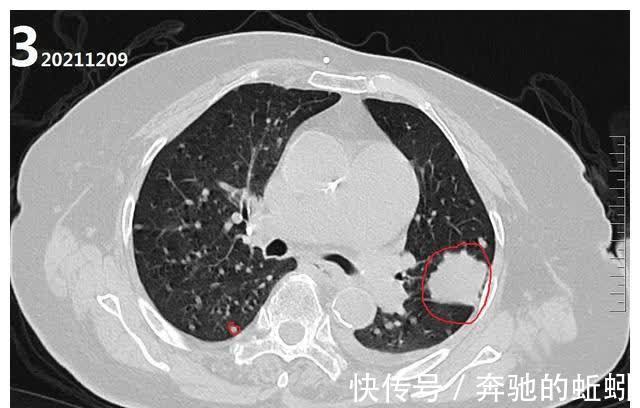

到了2021年12月9日,患者因右侧胸壁肿物,才来医院进行复诊。查CT,发现肺部情况如图3所示,左肺病灶无明显增大,但肺内可见无数个大小不等类圆形结节影。